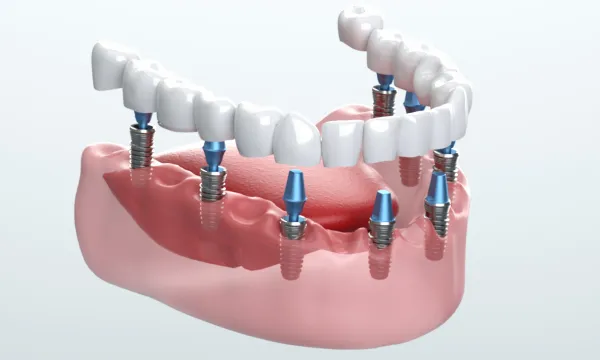

三重県津市の歯を失った方・歯がボロボロの方の治療専門である大杉歯科医院では、そのようなお悩みに応えるため、歯を失った・歯がボロボロの患者様に寄り添った全顎インプラント治療(オールオンフォー)や、見た目にも配慮した骨造成治療を行っています。機能性と審美性の両立を目指し、患者様が再び自然に笑顔で日常を送れるようサポートします。

総入れ歯を使用されている方の中には、「しっかり噛めない」「外れるのが怖い」と不便を感じている方が多くいらっしゃいます。オールオンフォーは、片顎に4本前後のインプラントを埋め込み、その上に取り外し不要の固定式の人工歯を装着する治療法です。違和感を抑えつつ安定感のある噛み心地を得やすいのが特徴です。

さらに、従来はインプラント治療が難しいとされてきた骨量の少ないケースでも、サイナスリフトやソケットリフトといった骨造成を組み合わせることで、治療の可能性を広げられる場合があります。「もう入れ歯しかない」と言われた方でも、固定式の歯で新しい日常を取り戻せるチャンスがあります。

さらに、オールオンフォーやオールオンシックスを用いることで、少ない本数で全体を支える固定式の歯を実現し、総入れ歯では得られない快適さを取り戻すことができます。

All-on-4/6の場合

多数の歯を失った場合に適応され、4~6本のインプラントで片顎全体を支える治療法です。総入れ歯と比べて外れる心配がなく、発音や会話も自然に近い状態を取り戻せます。

All-on-4/6とは?少ない本数で

Supporting Mechanism片顎4~6本で

12本相当を支える仕組み

オールオンフォー/シックスでは、奥歯のインプラントを斜めに埋入する独自の方法を採用します。これにより骨のある部分を有効に使い、片顎4~6本という少ない本数で全体を支えることが可能になります。

従来の治療では歯を失った本数に近い数のインプラントを必要とすることが多く、骨移植や大がかりな骨造成を伴うケースも少なくありませんでした。これに対しオールオンフォー/シックスは、骨の状態を最大限活かしながら安定した支持を得られるのが大きな特徴です。

さらに、インプラントは骨と結合する性質があるため、強固な土台として機能します。その上に装着する人工歯は色や形を調整でき、自然で快適な仕上がりを目指せます。